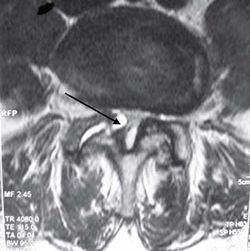

Скаленус-синдром. Одним из частых источников цервикобрахиалгии считают МФБС лестничных мышц. Боль локализуется в области плеча и над медиальным краем лопатки и распространяется по передней и задней поверхности плеча на лучевую часть предплечья, в большой и указательный пальцы (Рис. 2). Напряжение лестничных мышц происходит при удержании тяжелого предмета на уровне талии, при частых приступах кашля, участии мышц в парадоксальном дыхании, нахождении головы во время сна ниже уровня туловища, наклоне оси плечевого пояса, связанного с конституционально разной длиной ног, косым тазом, сколиозом.